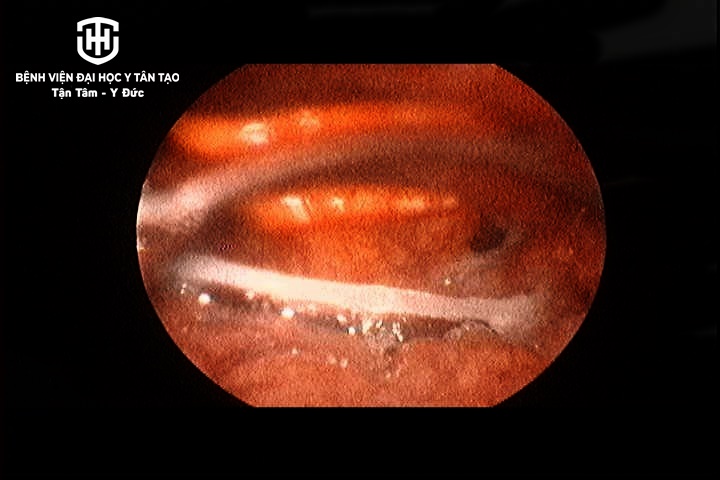

Bệnh nhận nhập viện vào chiều ngày 16/2 trong tình trạng đau vùng cổ, nhất là vùng dưới hầu họng, nuốt đau nghi do mắc xương cá trong lúc ăn uống tại gia đình. Qua nội soi, các bác sĩ xác định vùng hạ họng của bệnh nhân có nhiều dịch nhầy đục, nắp thanh thiệt sung huyết, vùng hạ họng đáy lưỡi có xương cá dài hơn 3cm.

Dị vật nằm ở vùng hạ họng bệnh nhân C., rất may bệnh nhân đến bệnh viện trong ngày khi bị mắc dị vật và được can thiệp kịp thời. Các bác sĩ đã tiến hành gắp dị vật ra bằng kẹp chuyên dụng qua nội soi, cổ họng bệnh nhân không còn đau, khó chịu, ít tổn thương, không để lại biến chứng. Bệnh nhân được xuất viện sau khi gắp dị vật.